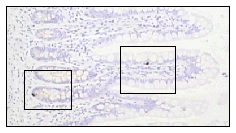

Administration of GLP-2 markedly decreased NSAID-induced

intestinal in mice, as shown below

Glucagon-like peptide 2 decreases mortality and reduces the severity of indomethacin-induced murine enteritis Am J Physiol 1999 Nov;277(5 Pt 1):E937-47 GLP-2, administered in a variety of regimens, reduces mortality and improves gross and microscopic indices of intestinal injury in mice with NSAID-induced enteritis